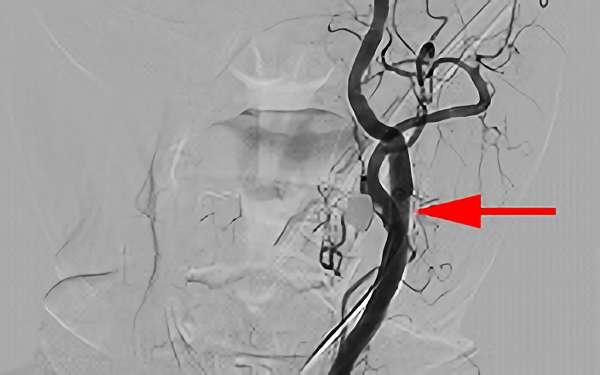

症例 '19年10月

No.

660

'19年10月8日

左内頚動脈狭窄症

70代

大阪府の病院

手術写真

治療

前

中

後

手術日